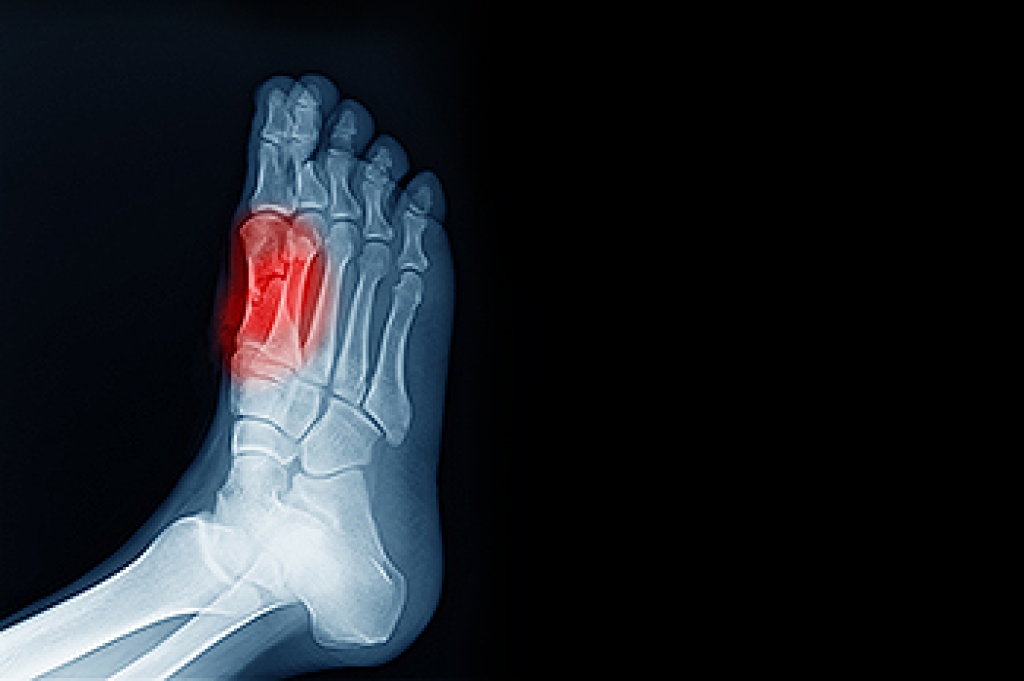

As people age, their feet often undergo physical changes that can lead to pain, instability, and reduced mobility. The natural thinning of fat pads, loss of skin elasticity, and decreased circulation can make older adults more prone to calluses, bunions, and hammertoes. Ingrown toenails and fungal infections also become more common, particularly when vision or flexibility limitations make it difficult to inspect and care for the feet. Poor balance or foot discomfort can increase the risk of falls, which are especially dangerous for seniors. Conditions like diabetes and arthritis may further affect the nerves, joints, and skin of the feet, raising the risk of infection or pressure-related injuries. A podiatrist can examine the feet, toes, and ankles for early signs of damage, treat existing conditions, and offer medical strategies to help preserve foot health in seniors. If you are a senior and have foot pain, it is suggested that you schedule an appointment with a podiatrist who can treat various foot conditions, and guide you on for regular foot health monitoring.

When people age, some common issues that may occur are bone density loss, dry skin, poor circulation, and rough brittle nails. These issues may also affect your foot health if the necessary steps are not taken to alleviate the problems.